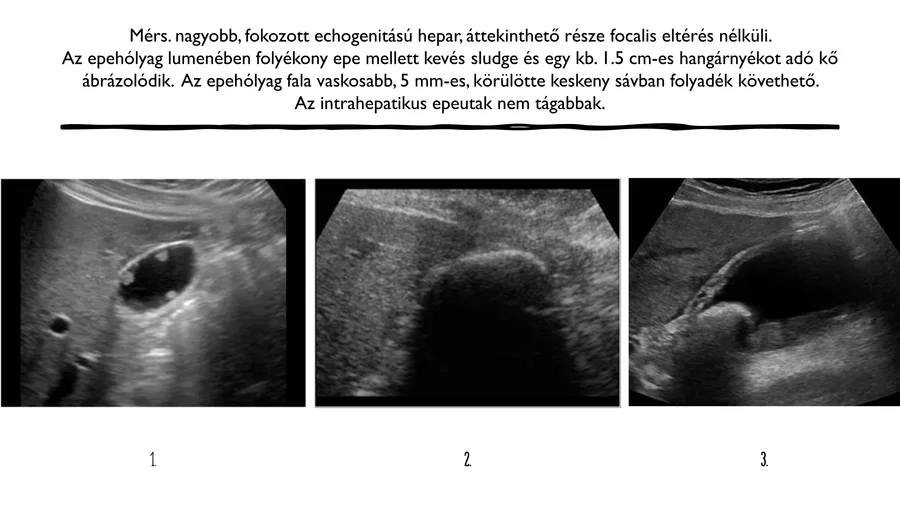

Melyik kép tartozik a lelethez?

1

2

3